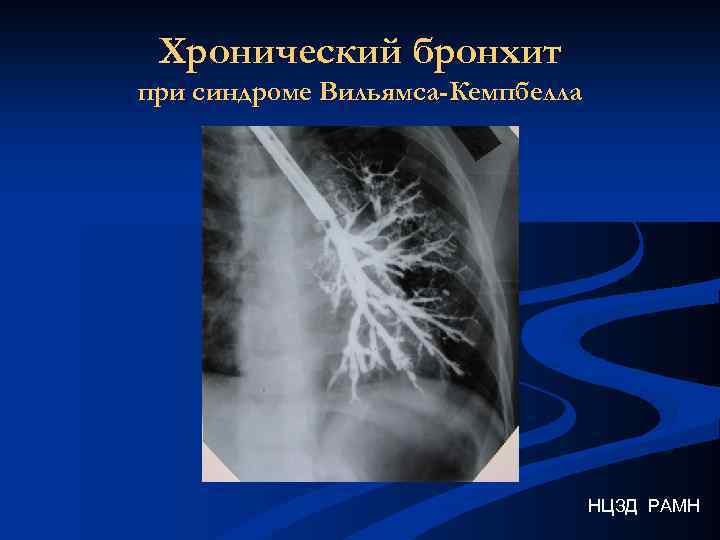

Хронический бронхит при синдроме Вильямса-Кемпбелла НЦЗД РАМН